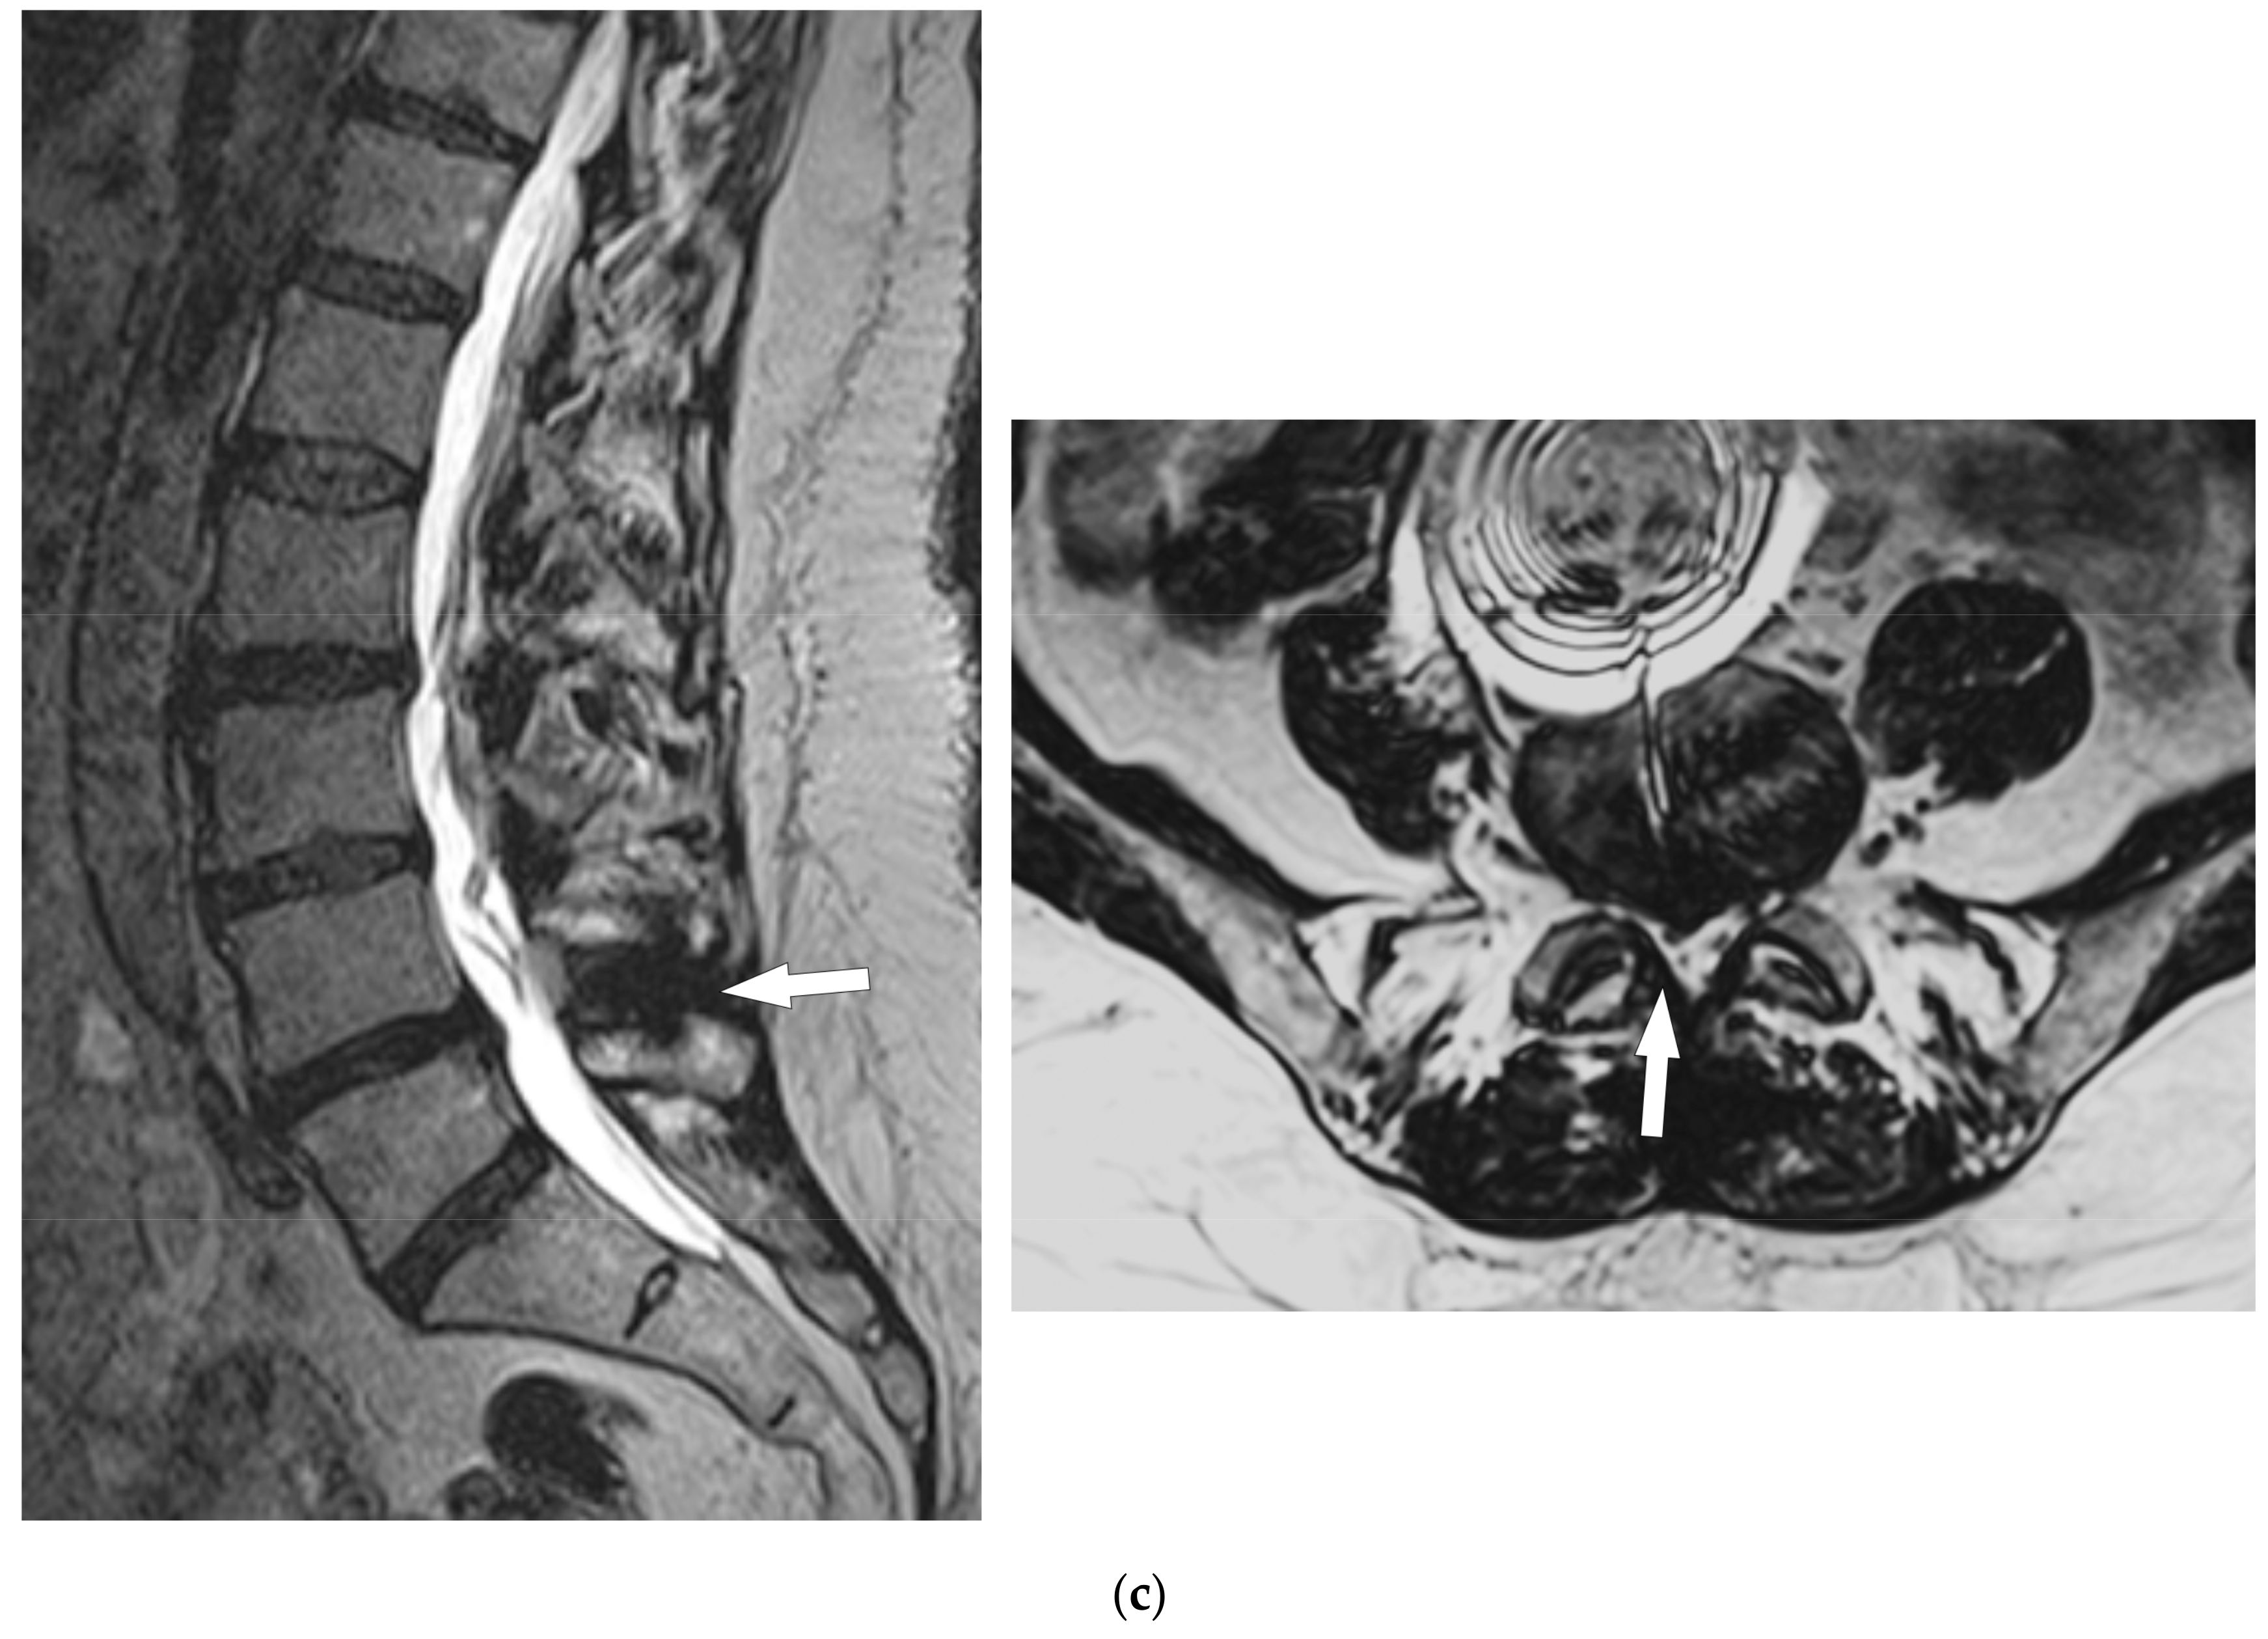

- Bonaldi, G.; Bertolini, G.; Marrocu, A.; Cianfoni, A. Posterior vertebral arch cement augmentation (spinoplasty) to prevent fracture of spinous processes after interspinous spacer implant. AJNR Am. J. Neuroradiol. 2012, 33, 522–528. [Google Scholar] [CrossRef]

- Manfré, L. Posterior Arch Augmentation (Spinoplasty) before and after Single and Double Interspinous Spacer Introduction at the Same Level: Preventing and Treating the Failure? Interv Neuroradiol. 2014, 20, 626–631. [Google Scholar] [CrossRef]